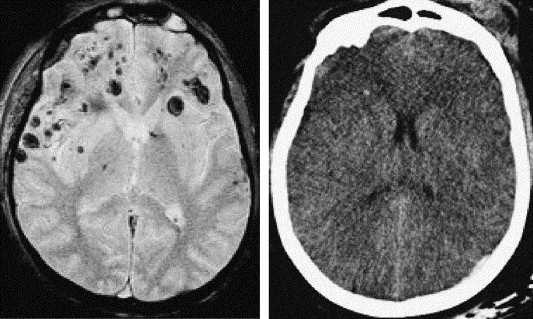

TDM

-Normal initialement dans 50 à 80% des cas >méconnait ++ les lésions -Lésions punctiformes hyperdenses spontanément – pétéchies hémorragiques. -Lésions punctiformes hypodenses non hémorragiques – œdème périlésionnel.

-T1 : hypersignal T1 des lésions pétéchiales hémorragiques. -T2 : Lésions pétéchiales hémorragiques de signal variable (dégradation de l’hémoglobine)

Lésion non hémorragiques en Hypersignal T2 -T2 EG : hyposignal des lésions pétéchiales hémorragiques (susceptibilité magnétique). - SWAN/SWI : Imagerie de susceptible magnétique haute résolution. pétechies +++ -Diffusion (+/- Tractographie): Foyers punctiformes en hypersignal diffusion - restriction ADC.